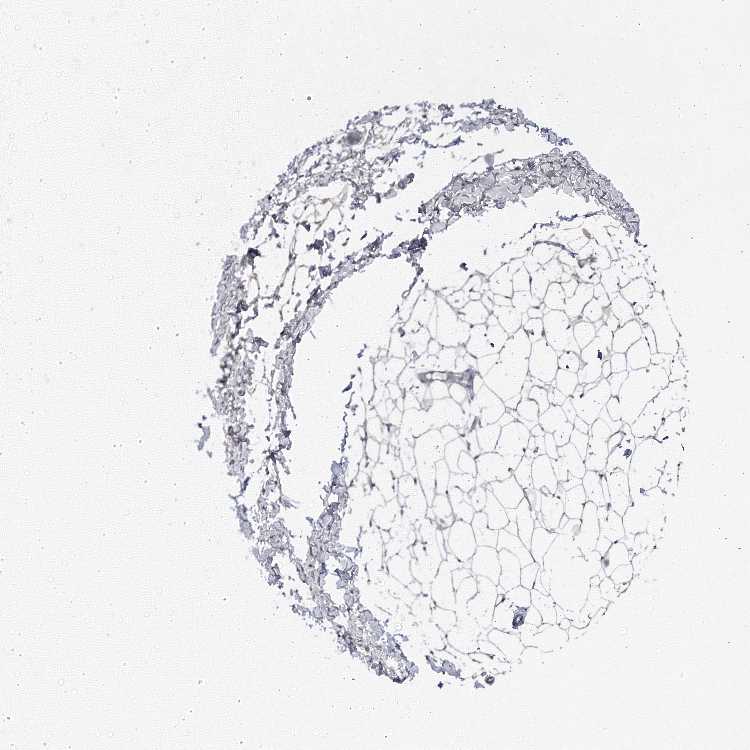

BREAST - Antibody stainingi

Antibody staining in the annotated cell types in the current human tissue is reported as not detected, low, medium, or high, based on conventional immunohistochemistry profiling in selected tissues. This score is based on the combination of the staining intensity and fraction of stained cells.

Each image is clickable and will lead to virtual microscopy that enables deeper exploration of all samples and also displays staining intensity scores, fraction scores and subcellular localization as well as patient and tissue information for each sample.

Antibody HPA039535Antibody HPA058867

Adipocytes Not detectedNot detected

Glandular cells MediumMedium

Myoepithelial cells LowMedium